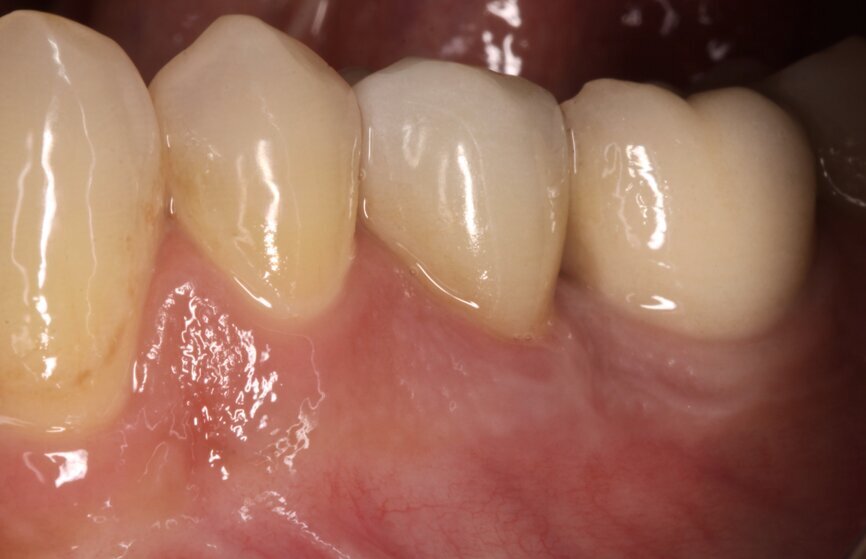

At the one-year follow-up visit, the soft-tissue contours adjacent to the implant restoration and the buccal bone volume and convexity still resembled those adjacent to the natural teeth. Bone levels around the implant appeared stable during radiographic evaluation (Fig. 9). No perceptible loss occurred. The artificial crown had an emergence profile mimetic of that of a natural tooth. At the two-year follow-up visit, the tissue contours looked stable and appeared even to have improved when compared with the one-year follow-up visit (Fig. 10).

Fig. 10: Clinical situation one year after treatment.